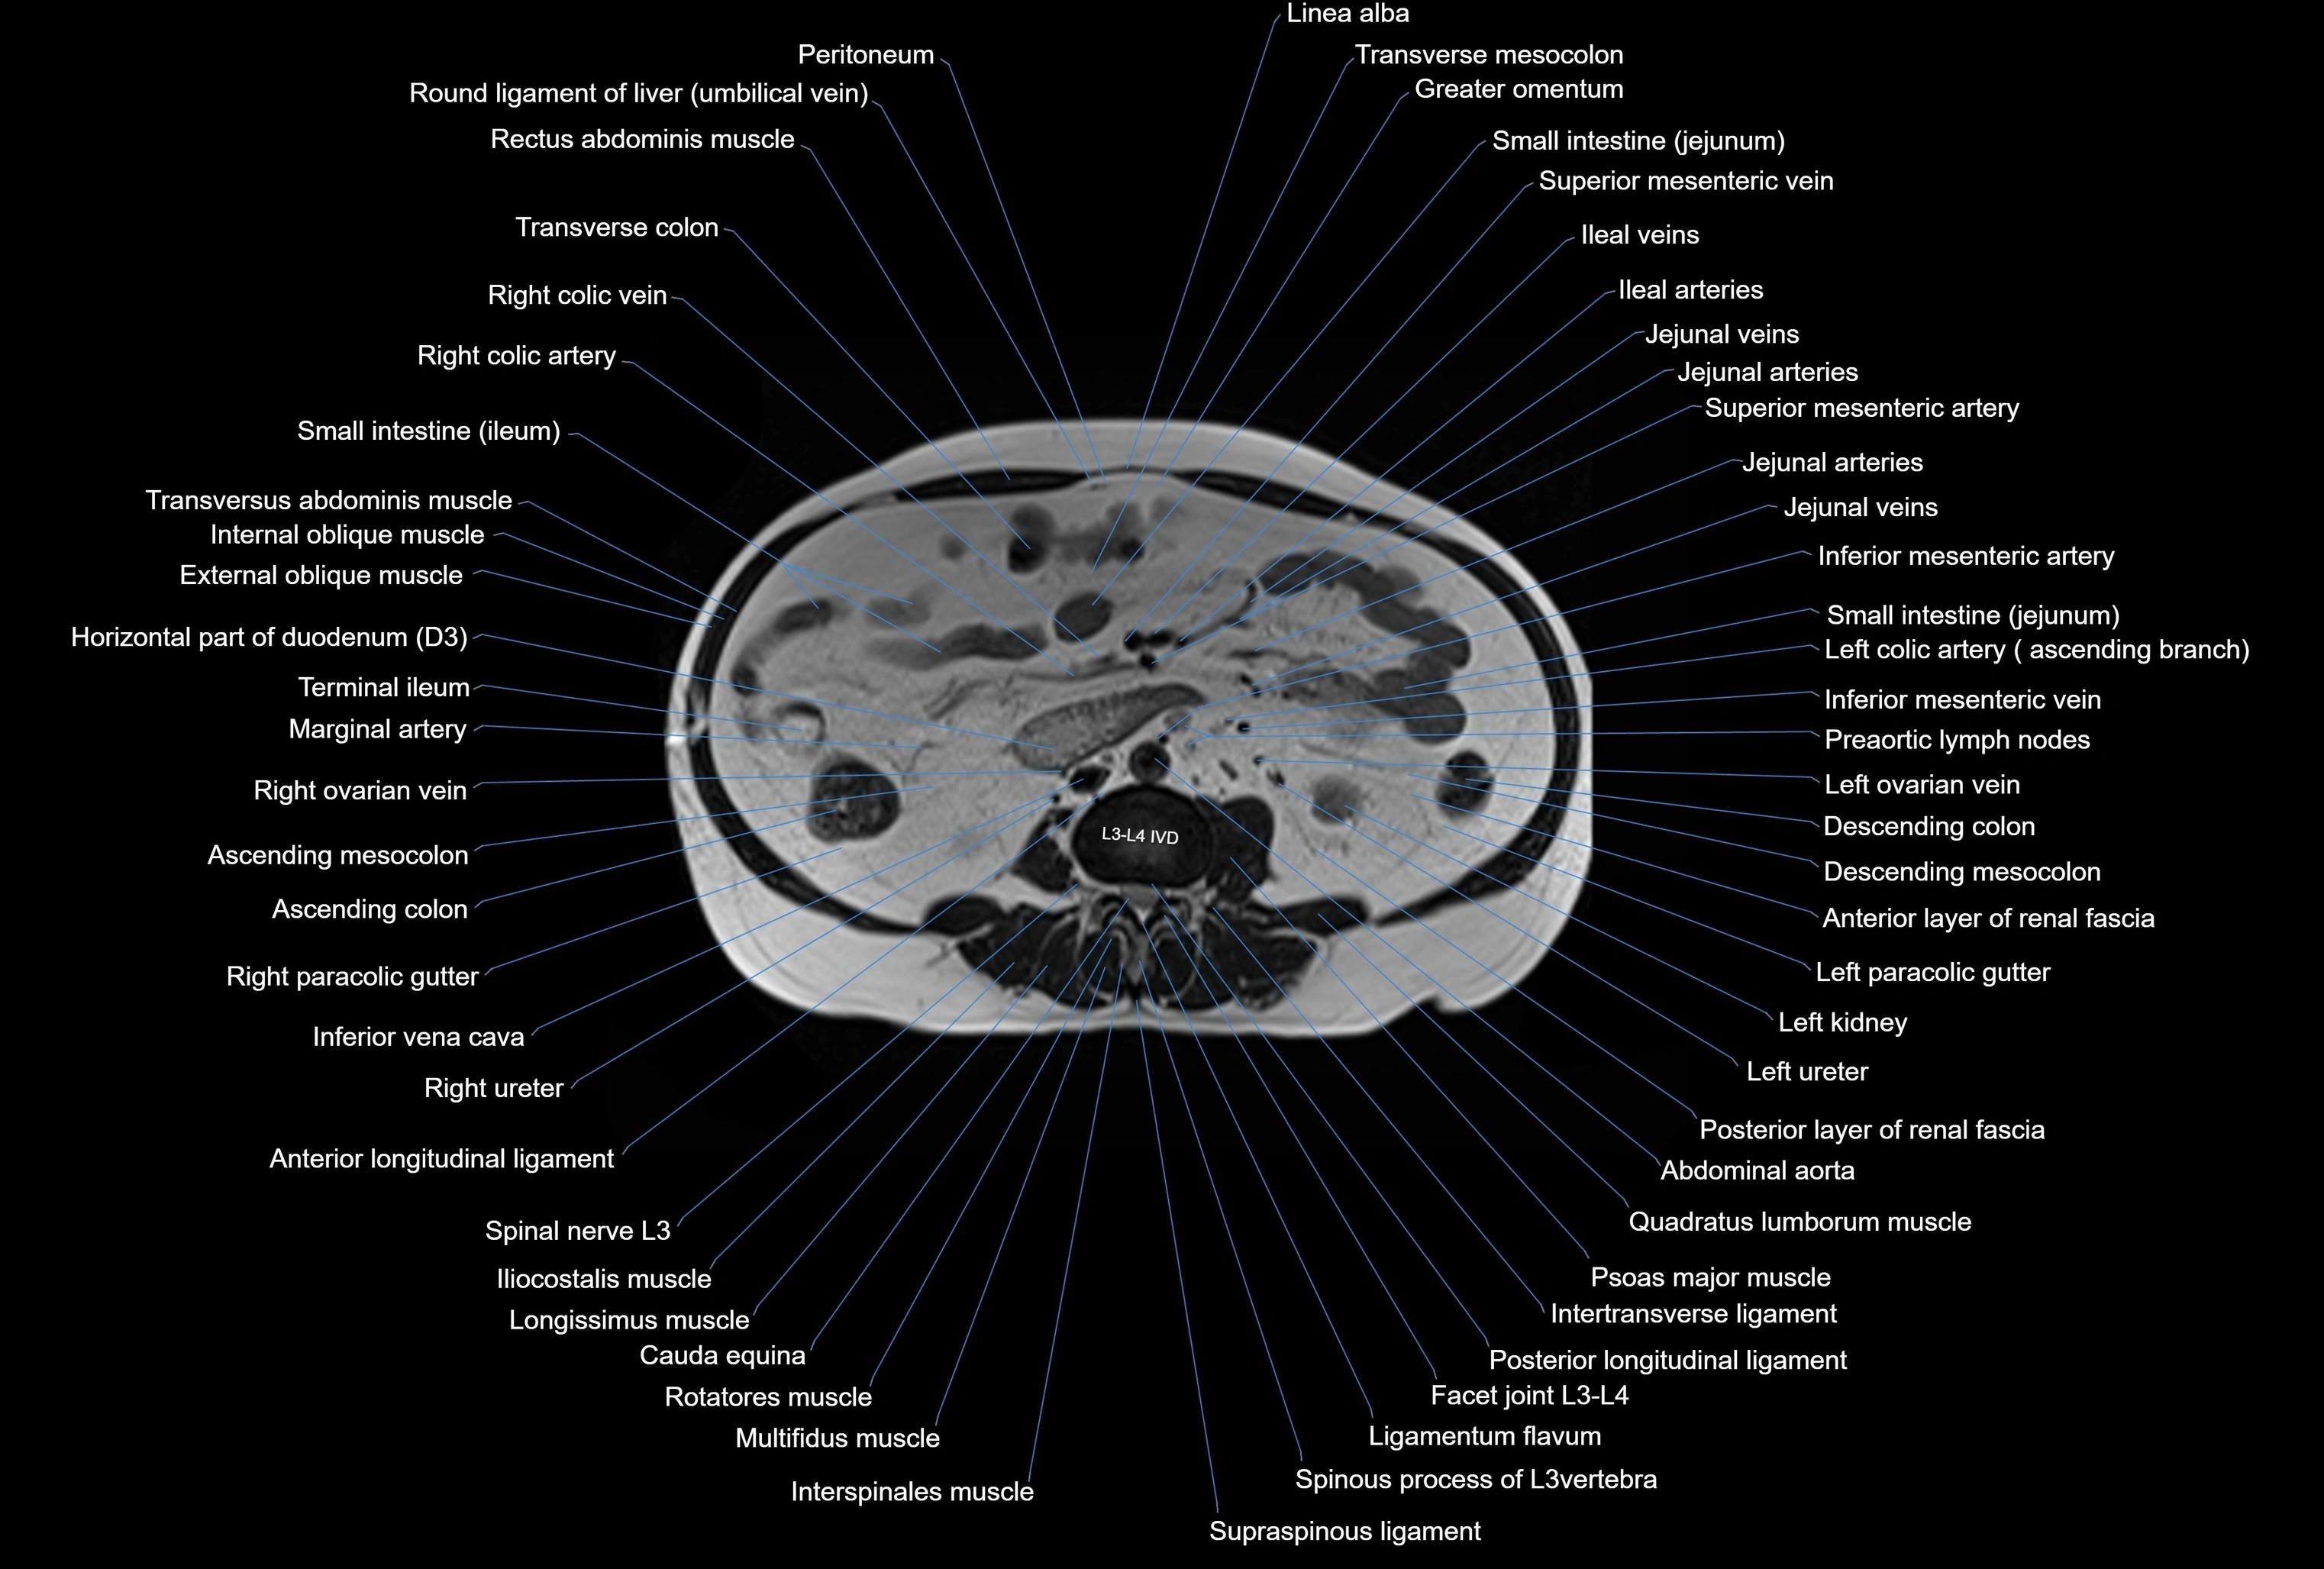

MRI images